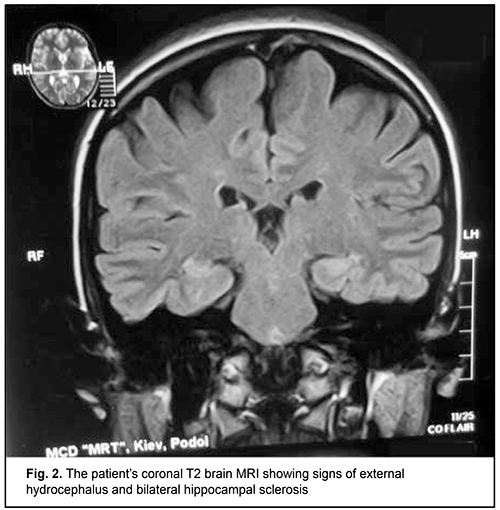

Although this immune deficiency is commonly compensated due to the activity of another microbicidal enzyme, NADPH oxidase, and does not result in severe clinical consequences [4], clinically manifested forms of the disease may occur and require special therapy [5]. Infections caused by opportunistic pathogens [6, 7] and some autoimmune, allergic, immunoinflammatory, and oncologic manifestations [8] have been described in patients with MPO deficiency. Particularly, individuals with such an immunoeficiency are prone to developing frequent attacks of or a severe episode of invasive candidiasis [9, 10]. The capacity of MPO to exert a virucidal effect with cytomegalovirus [11] and human immunodeficiency virus type 1(HIV-1) [12] have been demonstrated, and, therefore, some MPO-deficient patients have reduced resistance to opportunistic viral agents. Such autoimmune syndromes as rheumatic fever [13], multiple sclerosis [4] and rheumatoid arthritis [14] have been reported in MPO deficiency. Vasomotor dysfunction [15], parkinsonism [16], hemostasis hemostasis impairment [17], autism spectrum disorders [18] and impaired biological transformation of medications [19] are considered secondary immune deficiency syndromes, and associated with the pleiotropic nature of the biologic effects of MPO extending well beyond immune system function. A number of diagnostic laboratory assays for verification of MPO deficiency in human phagocytes are available, particularly automated hematography (a screening assay); flow cytofluorometry; biochemical assays including guaiacol peroxidation and alanine decarboxylation assays; spectroscopic analysis; enzyme immunoassay; immunoblotting; cytochemical techniques including benzidine and 4-Chloro-1-naphthol staining; immunocytochemical techniques; luminol-enhanced chemiluminescence of phagocytes; and electron microscopy [2, 20-23]. MPO deficiency should be differentiated from chronic granulomatous disease, neutrophil-specific granule deficiency, type I glycogenosis, hyperimmunoglobulin-E-recurrent infection (Job's) syndrome, Kostman's disease, Ch?diak-Higashi syndrome, adhesion molecule deficiency, and Shwachman syndrome, in which various phases of phagocytosis in neutrophils and monocytes/macrophages are impaired [2]. Primary MPO deficiency shows heterogeneous patterns of the complete deficiency state on the genomic level. The R569W missense mutation is a classic mutation described by Nauseef et al [1]. Nevertheless, Marchetti et al [24] conducted a study to investigate the nature of the mutations underlying the disease of the immune system. The genetic characterization of the subjects showed the presence of 3 already-known mutations (c.752T>C, c.1705C>T and c.1566_1579del14) and 6 novel mutations: four missense mutations (c.995C>T, c.1112A>G, c.1715T>G and c.1927T>C), than a deletion of an adenine within exon 3 (c.325delA) and a mutation within the 3’ splice site of intron 11 (c.2031–2A>C). As per the locally adapted National Evidence-based Guidelines [25] and Unified Clinical Pathway for Providing Primary, Secondary and Tertiary Care [26] in MPO deficiency in phagocytes, antimicrobial medications are administered in addition to basic treatment comprising recombinant human interferon gamma for compensation for immunodeficiency through an increase in the percentage content and functional activity of the affected enzyme in phagocytizing cells [27]. Although toxoplasma is a well-known opportunistic pathogen, until now, there have been no reports on the development of toxoplasmosis in primary MPO deficiency in humans. We present, to our knowledge, the first case of the development of toxoplasmosis in primary MPO deficiency in humans. A 25-year-old woman presented to a clinical immunologist (DVM) with complaints of weakness, fatigue, poor health, joint and muscle pain, and persistent hyperthermia (37.2-37.5 °C). She reported that she had been ill for the past 2 years and that her weakness had been progressive. In addition, the weakness had been severe over the past several months. Her physical examination was remarkable for congested posterior pharyngeal wall; hypertrophy of palatine tonsils; lymphadenopathy of submaxillary, anterior and posterior cervical, and axillary lymphatic nodes; and harsh breathing heard in the inferior portions of the lungs to auscultation. Her complete blood count was remarkable for absolute and relative lymphocytosis, but her erythrocyte sedimentation rate (ESR) was normal. Polymerase chain reaction (PCR) with primers specific for herpes viruses was positive for Epstein Barr virus (100,000 infectious units in a sample). The repeat PCR test demonstrated the same findings. In addition, the patient underwent ultrasonic examination of the thyroid gland, lung X-ray examination, and brain MRI. The results of these examinations, as well as serum pituitary, thyroid and gonad hormone levels were found normal. Conventional brain MRI showed signs of external hydrocephalus (expanded convex spaces and unusually deep sulci and thinned convolutions) and bilateral hippocampal sclerosis, the signs characteristic of infections with lymphotropic herpes viruses (Fig. 2).

Since no other cause for the clinical symptoms was established, weakness, poor health, and hyperthermia were thought to be associated with reactivated Epstein Barr virus infection. Therefore, the patient was administered double antiviral therapy with an acyclic analogue of guanosine, valacyclovir (3 g daily, orally) and recombinant human alpha-2b-interferon (3 mln units every other day, intramuscularly), in accordance with the findings of a recent controlled clinical study [28, 29]. After two months of this continuous combinatory antiviral therapy, no viral DNA in blood was detected, and, since her condition sharply improved, weakness was almost gone, and body temperature normalized, she was released from the clinic to be supervised by a family doctor. However, a year after her release from the clinic, her condition again worsened. She complained of light flashes in front of her eyes, blinking sensation, floating flies, moving black spots in the field of vision. In addition, decreased visual acuity, mixed conjunctival injection and increased sensitivity to light and tearing were noted. Because of the patient’s complaints, she was referred to the ophthalmologist, where she underwent ophthalmoscopy and fundus fluorescein angiography (FA); there were ophthalmoscopic signs of right eye chorioretinitis (Fig. 3). The right eye ophthalmoscopy found numerous retinal (including macular) foci. Fluorescein angiography showed pathological foci of hyperfluorescence in the macular and inferior temporal areas along vascular arcades in all phases. In addition, we revealed signs of retinal pigment epithelium atrophy. Such an ophthalmoscopic and FA picture of chorioretinitis may accompany an acute infection.